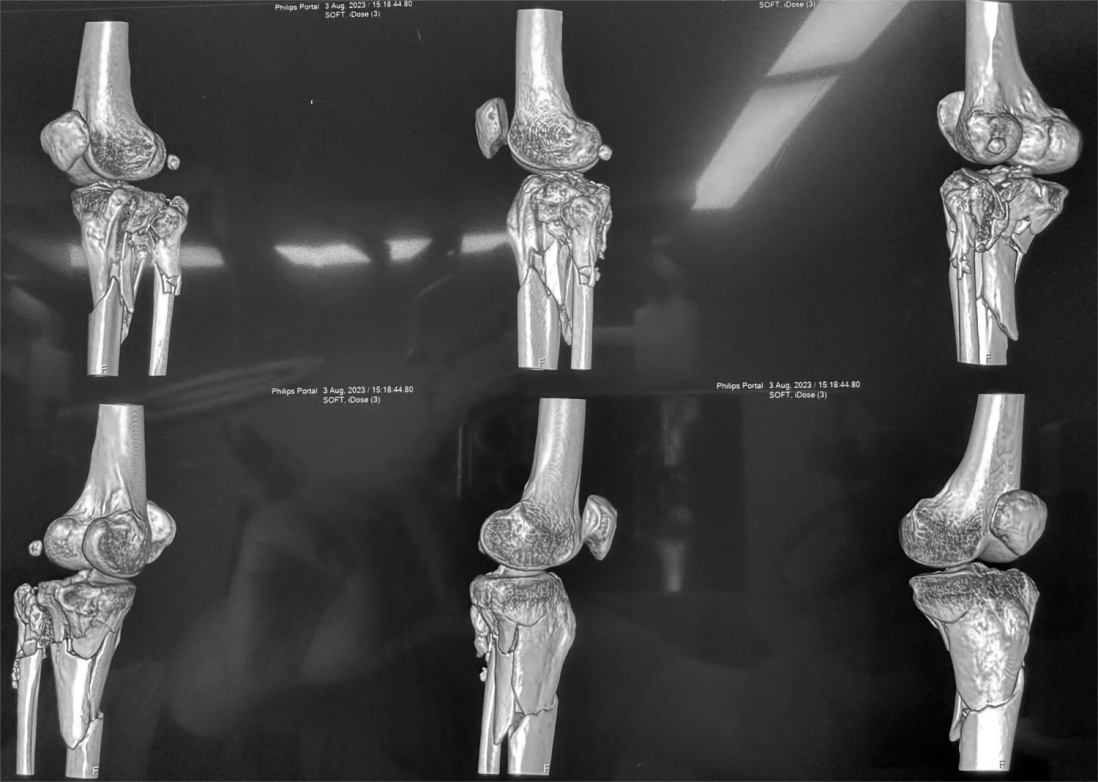

为深入贯彻党的二十大精神和习近平总书记关于深化东西部协作,落实“京蒙协作-医疗倍增计划”以及“公立医院高质量发展重点专科建设项目”,提升我院创伤急救外科水平,8月11日,我院特邀北京积水潭医院著名创伤外科专家刘亚波教授来院交流并进行复杂胫骨平台粉碎型骨折手术的演示指导。胫骨平台骨折手术一直以来是骨科手术中比较棘手的技术难题,治疗效果不太理想。通过刘亚波教授的手术演示、临床经验以及学术成果的分享,使我们对复杂胫骨平台手术以及创伤急救有了更广阔的发展思路。

患者CT+三维重建